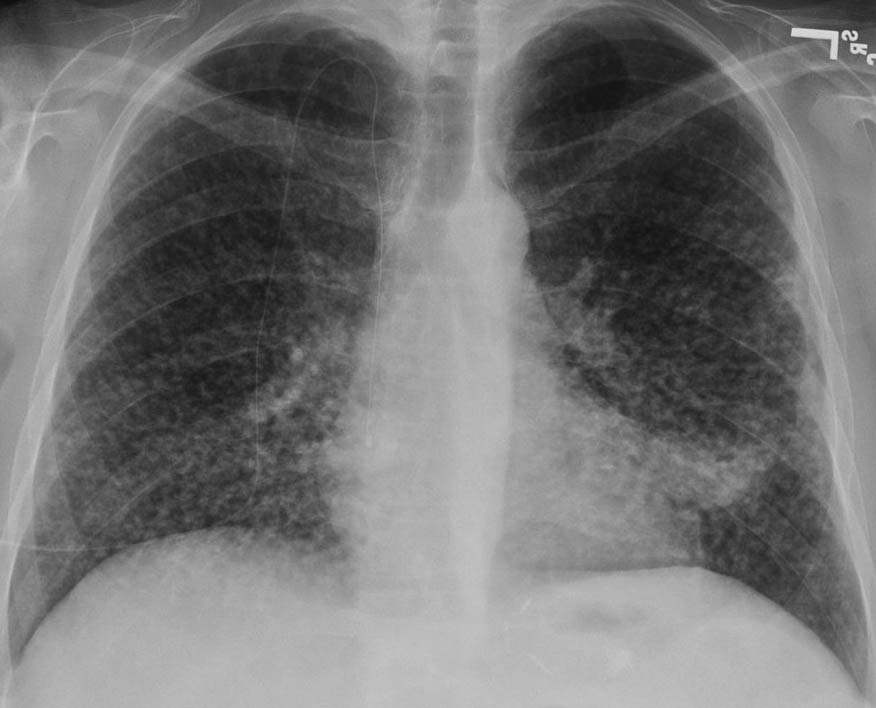

Explanation: ***Environmental occupational exposure*** - 20 years of **construction work** leads to prolonged exposure to **asbestos** and **silica dust**, causing characteristic chest x-ray findings like **interstitial opacities**, **pleural plaques** (asbestosis), or **upper lobe nodules** with **eggshell calcifications** (silicosis). - The combination of **smoking history** and **occupational dust exposure** significantly increases the risk of developing **pneumoconiosis** and related pulmonary complications. *Chronic bronchitis* - Typically presents with **productive cough** with purulent sputum for at least 3 months per year for 2 consecutive years, but doesn't cause specific chest x-ray abnormalities. - While smoking is a risk factor, chronic bronchitis usually shows **normal chest x-ray** or **increased bronchovascular markings**, not the interstitial changes expected from occupational exposure. *Empyema* - Characterized by **infected pleural fluid** collection, presenting with **fever**, **pleuritic chest pain**, and **systemic toxicity**. - Chest x-ray would show **pleural effusion** with **air-fluid levels** if complicated, not the interstitial patterns typical of occupational lung disease. *Congestive heart failure* - While the **lateral wall ischemia** on ECG suggests cardiac involvement, CHF typically causes **bilateral lower lobe infiltrates**, **cardiomegaly**, and **pulmonary edema**. - The **ECG finding** is likely a **distractor** and not the primary cause of the chest x-ray changes, which are more consistent with occupational lung disease from construction work exposure.